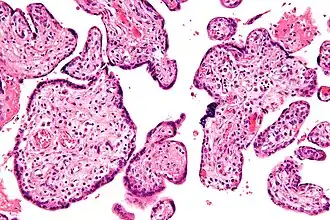

![]() Micrografía de vilitis de etiología desconocida. Tinción H&E. | ||

Histomorfológicamente, la VUE se caracteriza por un infiltrado linfocitario de las vellosidades coriónicas sin una causa demostrable. Las células plasmáticas deben estar ausentes; la presencia de células plasmáticas sugiere una etiología infecciosa, por ejemplo, infección por CMV.